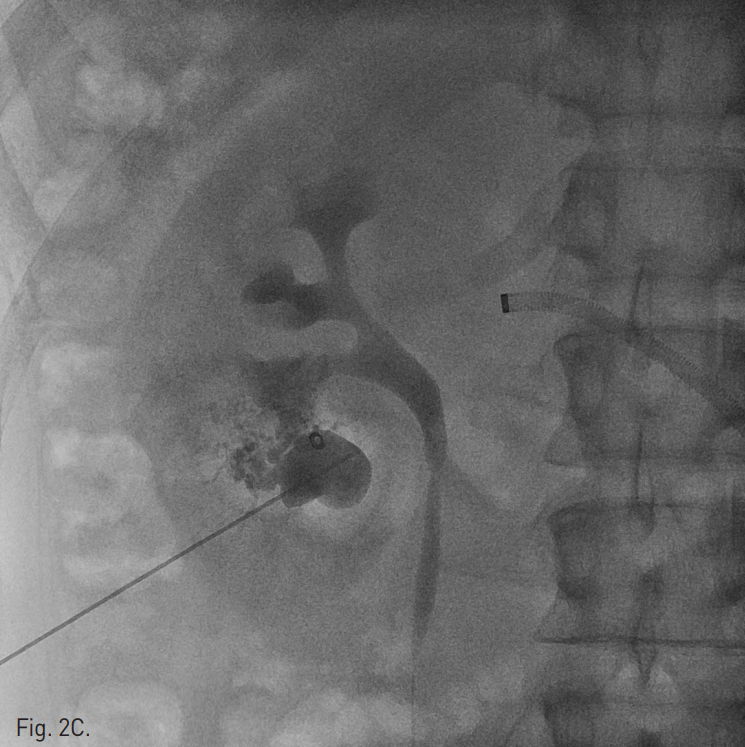

이어 환자를 복와위로 돌려눕히고, 초음파 유도하에 21G Chiba needle로 nidus를 직접 천자 후 혈관조영술을 시행하여 동정맥기 형의 nidus와 유출정맥을 확인하였다(Fig. 2B). Chiba needle을 통하여 3mm × 2cm Tornado coil(Cook, Bloomington, IN)을 nidus에 넣자 유출정맥의 기시부가 매우 좁아서 유출정맥의 입구에 걸려 혈류가 느려졌다. 이후 Gelfoam을 소량 주입하여 혈류가 거의 없어짐을 확인한 뒤, Chiba needle을 nidus의 가장 깊은 위치에서부터 후진시키며, 99% 알코올을 소량씩 주입하여 색전을 시행하였다(Fig. 2C). 색전술 후 시행한 왼쪽 신장동맥 혈관조영술에서 동정맥기형은 더 이상 관찰되지 않는다(Fig. 2D).

C. A radiograph obtained during alcohol injection shows a coil occluding venous outflow tract and reflux of the contract media into afferent arterioles.